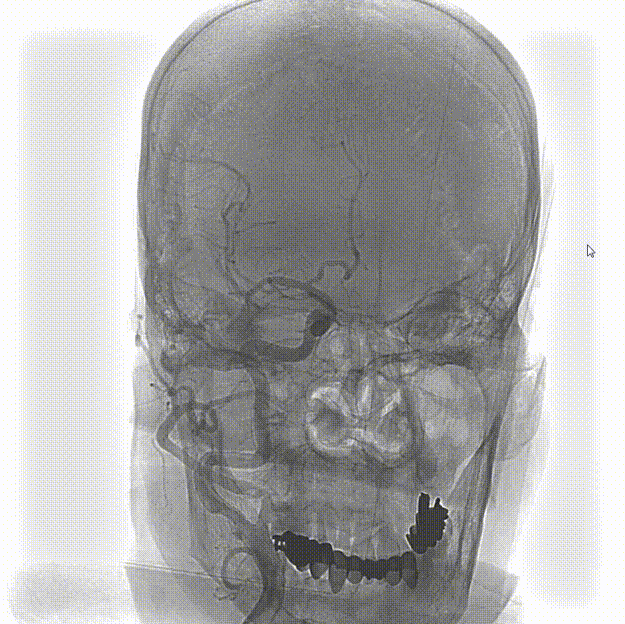

头颅CT(2024-07-25,外院):双侧基底节区,放射冠腔隙性脑梗死。

患者取平卧位置,常规消毒、铺巾和局麻右侧腹股沟下穿刺点后,穿刺置入5F动脉鞘,再以5F单弯行选择性脑动脉造影。造影示:II型主动脉弓,右侧颈内动脉C1段重度狭窄。

左侧颈动脉未见明显异常。

造影显示左侧椎动脉V1段中重度狭窄。